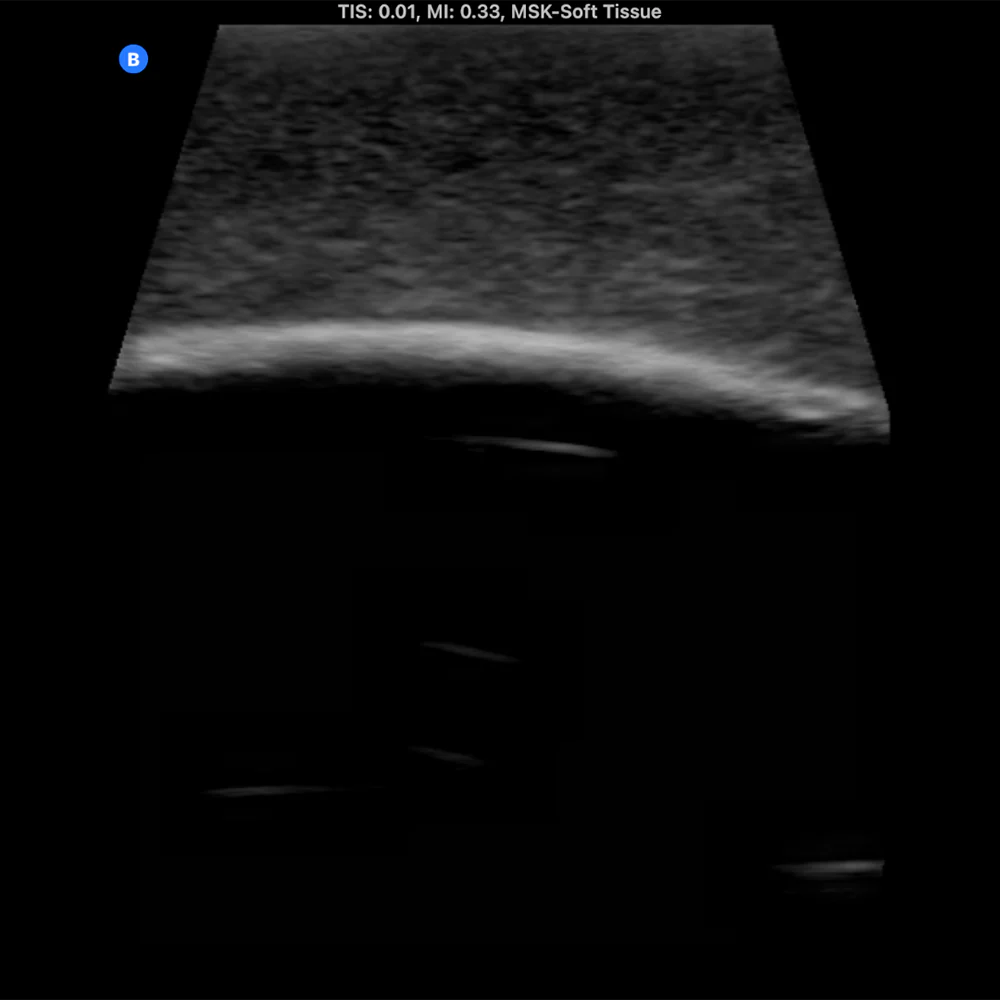

The Bone Fracture Ultrasound Phantom is an excellent training aid for developing the skills needed to identify bone fractures within soft tissue.

- Five bones incorporated within the model (three positioned superficially and two at a deeper level).

- One healthy bone with no fracture, plus four bones featuring fractures of varying severity.

- Produces outstanding ultrasound image quality.